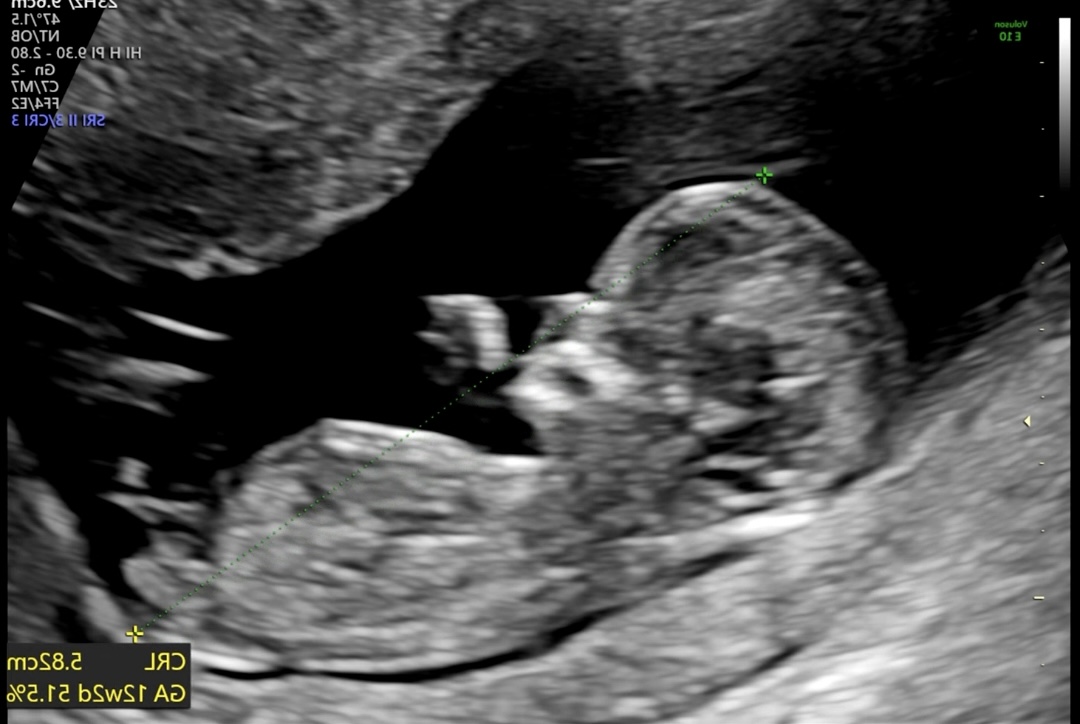

📸나의 12주차 초음파 사진과 장꾸맘의 예측

저는 임신 12주 차에 1차 기형아 검사를 하면서 초음파사진과 원본 동영상을 장꾸맘 카페에 올려서 각도법을 문의했어요!

그리고 3일 정도 뒤쯤에 장꾸맘님께서 조심스럽게 아들에 한 표라고 하시더라고요

12주 차 각도법으로 아들이라고 했던 장꾸맘님이 맞췄습니다..................

16주 차 2차 기형아검사를 하러 갔더니 고추가 딱!!!!!!!!!!!

어어.,.? 딸이라고 했는데요? 했더니 고추가 이렇게 있다고... 아들이라고...

정말 놀랍게도 장꾸맘 각도법이 맞았고 병원에서 틀렸어요...